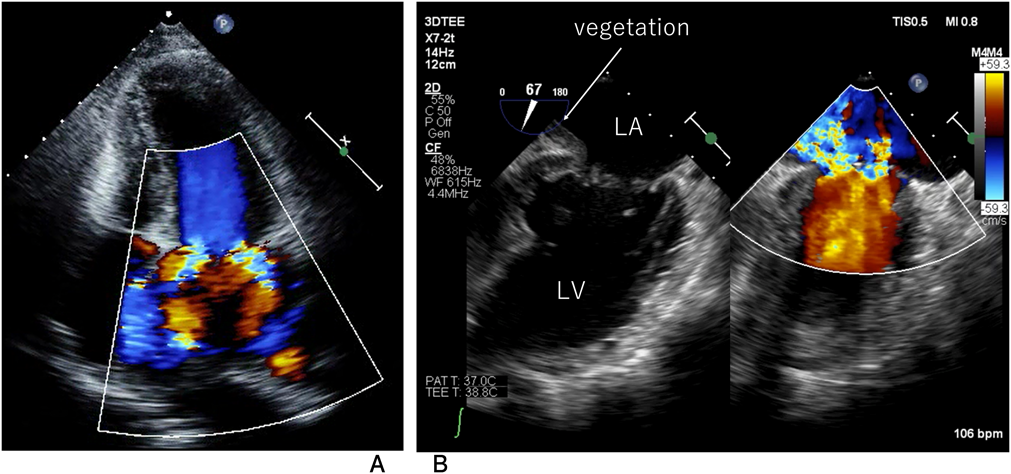

A 30-year-old woman was diagnosed with WS due to a characteristic face and SAS after birth. The Doty procedure was performed at the age of 5 years. Although SAS was relieved, mitral valve prolapse and mitral regurgitation were detected at the age of 10 and progressed to a grade of III at the age of 20. She presented with mental retardation associated with behavioral problems. Removal of teeth plaque was required every 3 months because of malocclusion and dental caries. She was admitted to our hospital because of a remittent fever one month before admission and dyspnea one week before admission after a dental procedure without prior administration of prophylactic antibiotics. On admission, she had a high-grade fever, dyspnea, her eyelids and bilateral lower legs were markedly edematous, and she displayed weight gain of 10 kg in 2 weeks. The resting heart rate was irregular, and auscultation revealed a grade 2/6 regurgitant systolic murmur at the apex. Complete blood counts showed a white blood cell level (WBC) of 1.10×1010/L, a hemoglobin level of 12.5 g/dL, and a platelet level of 143×109/L. The levels of C-reactive protein (CRP) and B-type natriuretic peptide were 0.52 mg/dL (normal range<0.14 mg/dL) and 352.7 pg/mL (normal range<18.4 pg/mL), respectively. Chest radiography showed cardiomegaly, bilateral pulmonary congestion, and bilateral pleural effusion (Fig. 1A). Electrocardiography revealed atrial fibrillation that had never been diagnosed (Fig. 1B) and transthoracic echocardiography revealed left atrium dilatation, mitral valvular anterior leaflet prolapse, and severe mitral regurgitation (Fig. 2A). In transesophageal echocardiography, isoechoic vegetation was identified on the left side of the atrial septum, the impact site of the mitral regurgitant stream (Fig. 2B). Two sets of blood culture were positive for Streptococcus gordonii, which is sensitive to penicillin G and ampicillin. Electrical cardioversion (100 J) restored sinus rhythm, and the patient was subsequently treated with intravenous ampicillin and gentamicin. She became afebrile the next day, and blood cultures were sterile on day 12 of hospitalization. WBC and CRP levels normalized by day 27, and the vegetation disappeared completely on day 43. Antibiotic administration was discontinued on day 44. The degree of mitral regurgitation remained severe despite the improvement in symptoms and laboratory data. Consequently, we performed mitral annuloplasty, pulmonary vein isolation, and left appendage closure 3 months after admission. The anterior mitral leaflet was large and thick, and the posterior leaflet was smaller in dimension (Fig. 3A). An incision was made on a part of the anterior mitral leaflet, and plication of the bilateral commissure was performed. The resected specimen of the mitral valve showed minimal chronic inflammation with myxoid degeneration (Fig. 3B). She was discharged on day 14 after surgery without any complications.

Fig. 2 (A) Transthoracic echocardiography shows left atrium dilatation, mitral valvular anterior leaflet prolapse, and severe mitral regurgitation. (B) Transesophageal echocardiography demonstrates isoechoic vegetations (white arrow) at the atrial septum, where the regurgitant jet impacts. LA, left atrium; LV, left ventricle.